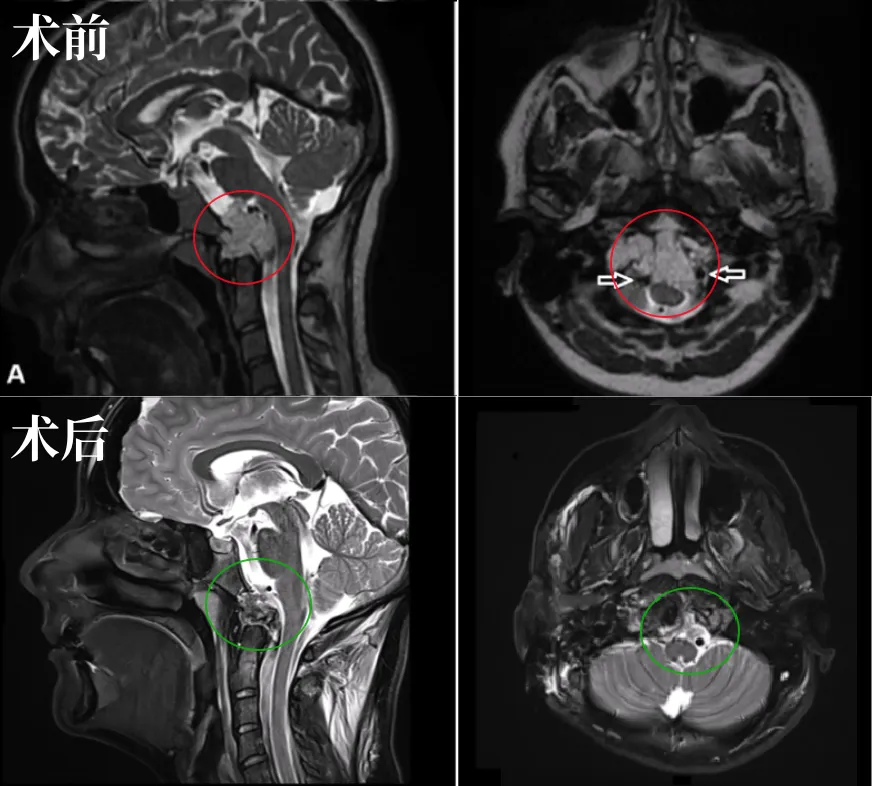

▼48岁男性反复复发高难度鞍区脊索瘤

点击查看案例详情:生死营救较大脊索瘤复发患者!INC法国Froelich教授5月中国行高难度示范手术

▼21岁女性颅颈交界区脊索瘤

点击查看案例详情:INC法国Froelich教授-前外侧入路“双镜手术”全切颅颈交界区脊索瘤